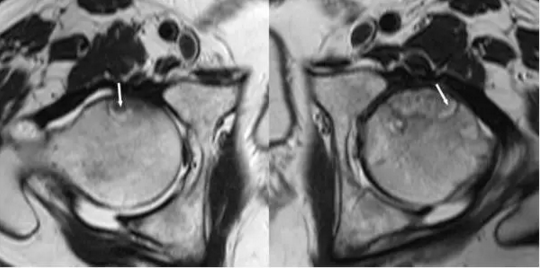

股骨头缺血坏死

该患者病程6个月,患者两侧缺血坏死,经过了骨内减压术后,右侧股骨头近端已经轻度扁平化,这表明疾病从阶段2到阶段3的进展,尽管保守治疗。 右侧近端股骨头内的缺陷代表死骨的移除。